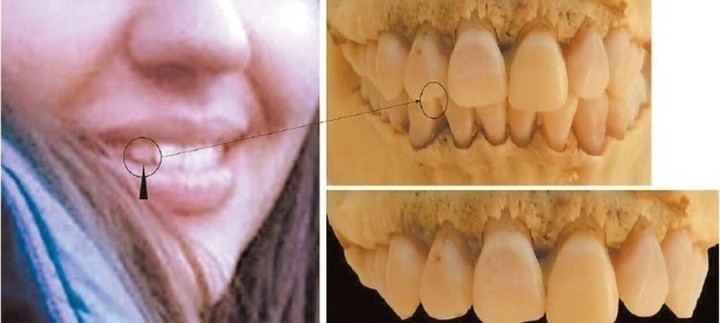

El Tribuno publicó las comparaciones, hechas por el doctor Oscar H. Heit, de Entre Ríos, y su par salteño Pablo Medina en contacto con una dentista forense de Bolivia, que les pidió colaboración para tratar de identificar la dentadura.

Las fotos fueron incorporadas al expediente judicial. Se habla de “múltiples coincidencias”: una grieta en uno de los incisivos, la forma del mentón y las inclinaciones de otras piezas dentarias.